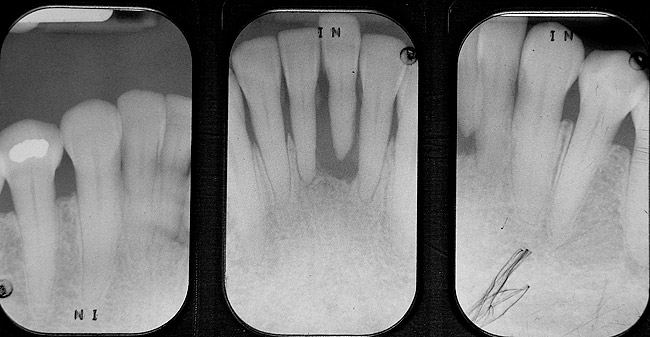

When fiber-reinforcing materials were introduced, the focus for their use was for periodontal splinting and stabilization resulting from tooth mobility.6,10,16,41-43 There is no doubt that splinting does reduce tooth mobility while the splint is in place.44 In the last decade, research supports the use of periodontal splinting as recommended therapy to stabilize those teeth to improve long-term prognosis.45-47 In a long-term clinical evaluation of splinting over a period of 48 to 96 months, using the original Ribbond Reinforcement Ribbon in fiber-reinforced composite resins was highly successful.17 The success of these splints can be attributed to close adaptation of the fiber ribbon to the tooth surface combined with cross stabilization of the mobile teeth by placing adhesive composite resin on the facial surfaces (Figure 4A, Figure 4B, Figure 4C, Figure 4D, Figure 4E).34,35 Splinting of traumatized teeth with fiber-reinforcing materials and adhesive composite resin has also been reported.48,49 When using fiber to stabilize the traumatized tooth or teeth or for tooth stabilization after re-implantation, the tooth must be allowed to have some movement and not be fixed in place.50,51